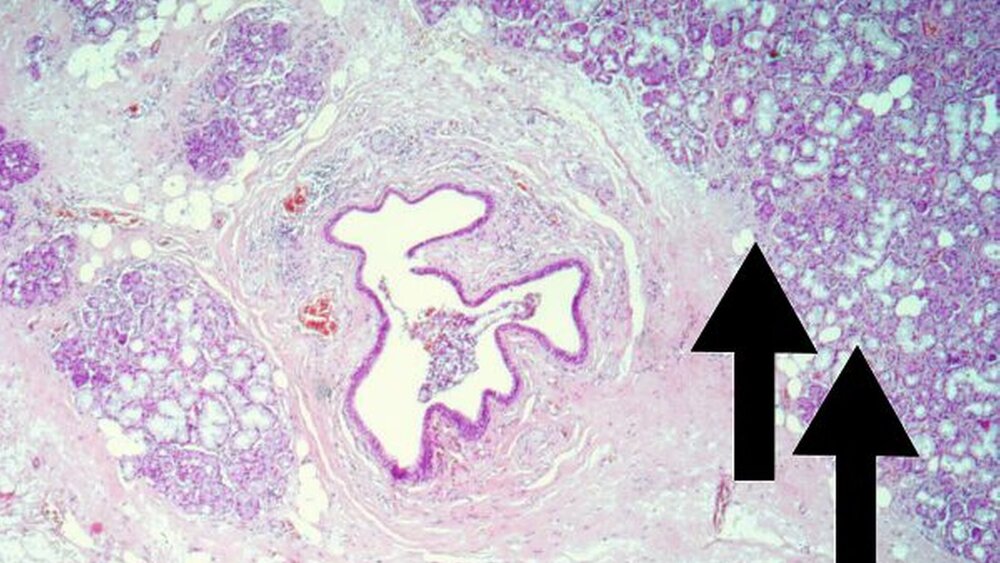

Die klinische Untersuchung zeigte extraoral ein 1,2 cm x 1,0 cm großes, gering gerötetes Hautareal submandibulär rechts (Abbildung 1) mit zentraler Einziehung, welche in einen Gang mündet. Intraoral fand sich ein saniertes, durch parodontalen Abbau gekennzeichnetes Gebiss mit einem bedingt erhaltungswürdigen Zahn 33 (Abbildung 3). Hier waren keine pathologischen Veränderungen der Mundschleimhaut erkennbar. Die präoperativ durchgeführte sonographische Untersuchung der Kopf-Hals-Region zeigte weder einen Anhalt auf ein Tumorrezidiv im Bereich des ehemaligen Operationsgebietes noch malignitätsverdächtige Lypmhknotenschwellungen. Kaudal des Unterkiefers rechts ist im Ultraschall keine Glandula submandibularis abgrenzbar. Es erfolgte die operative Entfernung des Fistelmauls inklusive des tiefer liegenden Drüsengewebes in Lokalanästhesie unter Darstellung und Schonung des Ramus marginalis mandibulae des Nervus facialis. Das entnommene Präparat (Abbildung 4) wurde zur histologischen Aufbereitung in die Pathologie eingesandt. Die histopathologische Aufarbeitung des Präparates zeigte Reste von Drüsengewebe mit dichten periduktalen, rundzelligen Entzündungsinfiltraten. Teilweise fanden sich im Bereich des Ausführungsganges plattenepitheliale Metaplasien sowie Zeichen der Sialadenitis und Lipomatosis (Abbildung 5).